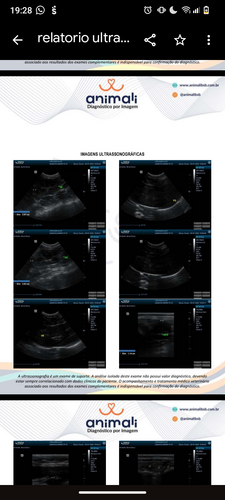

Eu sou a Victoria e criei esta vaquinha com o coração apertado para arrecadar R$ 1.200,00 valor necessário para a cirurgia urgente da minha gatinha, Café. Recentemente, ela recebeu o diagnóstico de piometra, uma infecção uterina grave que pode tirar sua vida se não for tratada a tempo.O procedimento me pegou completamente desprevenida, e por isso qualquer ajuda faz uma diferença enorme. Seja com uma doação, seja compartilhando esta vaquinha, você estará ajudando a salvar a vida de uma gatinha cheia de amor para dar.A Café é pequena, doce e muito amada e será eternamente grata por cada gesto de carinho recebido ao longo da vidinha dela.